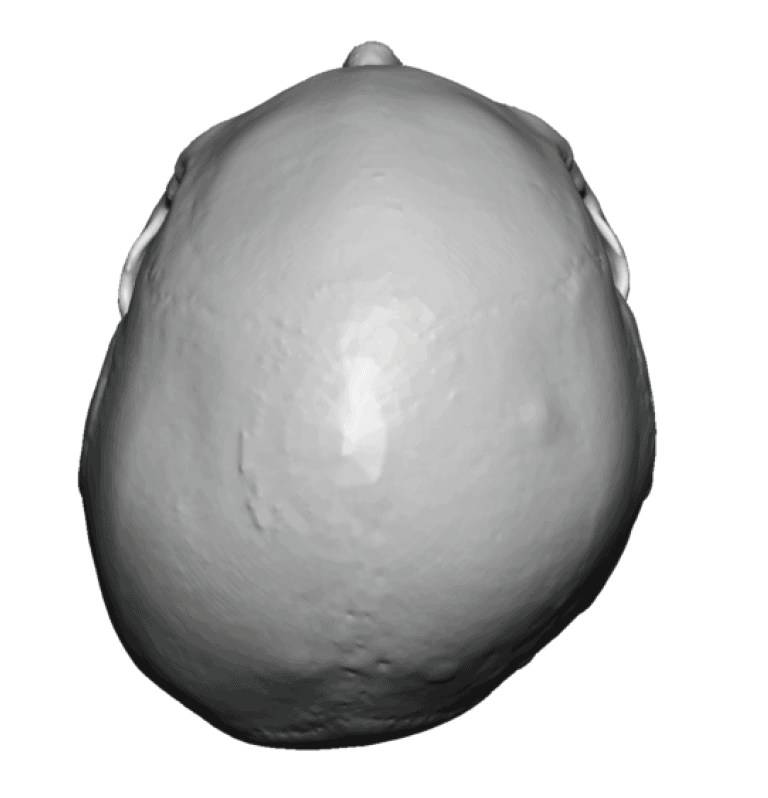

Desire for rounder shape to the top of the head from a congenital parasagittal deficiency skull shape.

Custom skull implant designed to fill in the parasagittal deficiencies.

Desire for rounder shape to the top of the head from a congenital parasagittal deficiency skull shape.

Custom skull implant designed to fill in the parasagittal deficiencies.